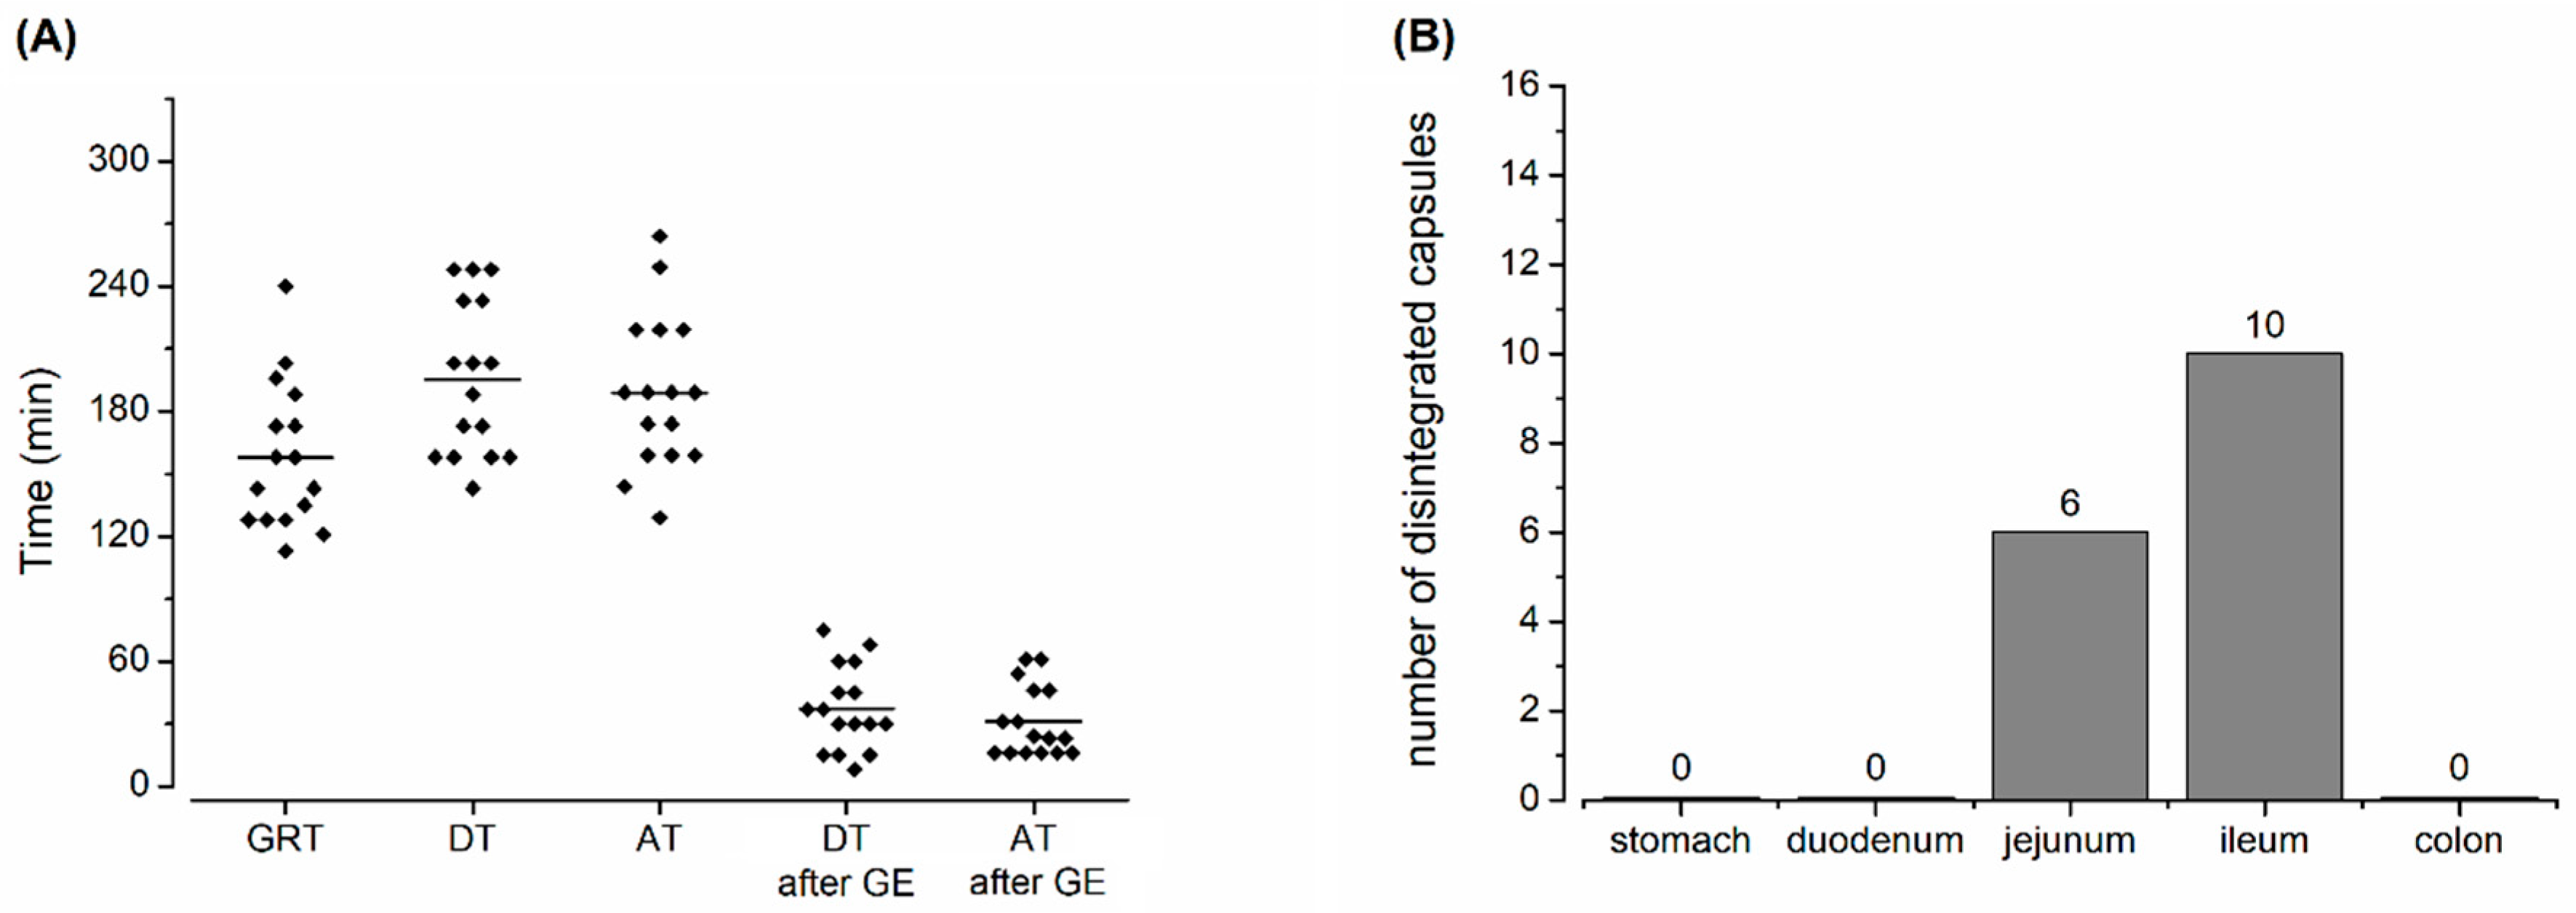

2.4. Salivary Sample Preparation and Evaluation of Caffeine Pharmacokinetics

2.5. Magnetic Resonance Imaging Sequences

2.6. Image Analysis

2.7. Capsule Evaluation Criteria

3. Results and Discussion